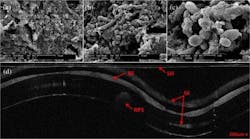

The current method for biofilm characterization utilizes scanning electron microscopy (SEM), a lengthy process that requires extracting a sample, drying it, and coating it with a thin gold layer, none of which can be performed in vivo. OCT, on the other hand, is a noninvasive imaging technology that can provide high-resolution, cross-sectional images of various biological samples, and can be adapted to provide 3D volumetric information.

In the research team's study, led by researcher Andrew Heidari, they extubated patients' endotracheal tubes and imaged them using both OCT and SEM. Biofilm was present in both images, and the researchers were able to use the OCT image to measure a reduction in endotracheal inner lumen area between a one-day intubation sample tube and a five-day sample tube. The study showed that OCT can be used to both detect the presence of biofilm and gather further information about the extent of biofilm formation from the thickness of biofilm observed.